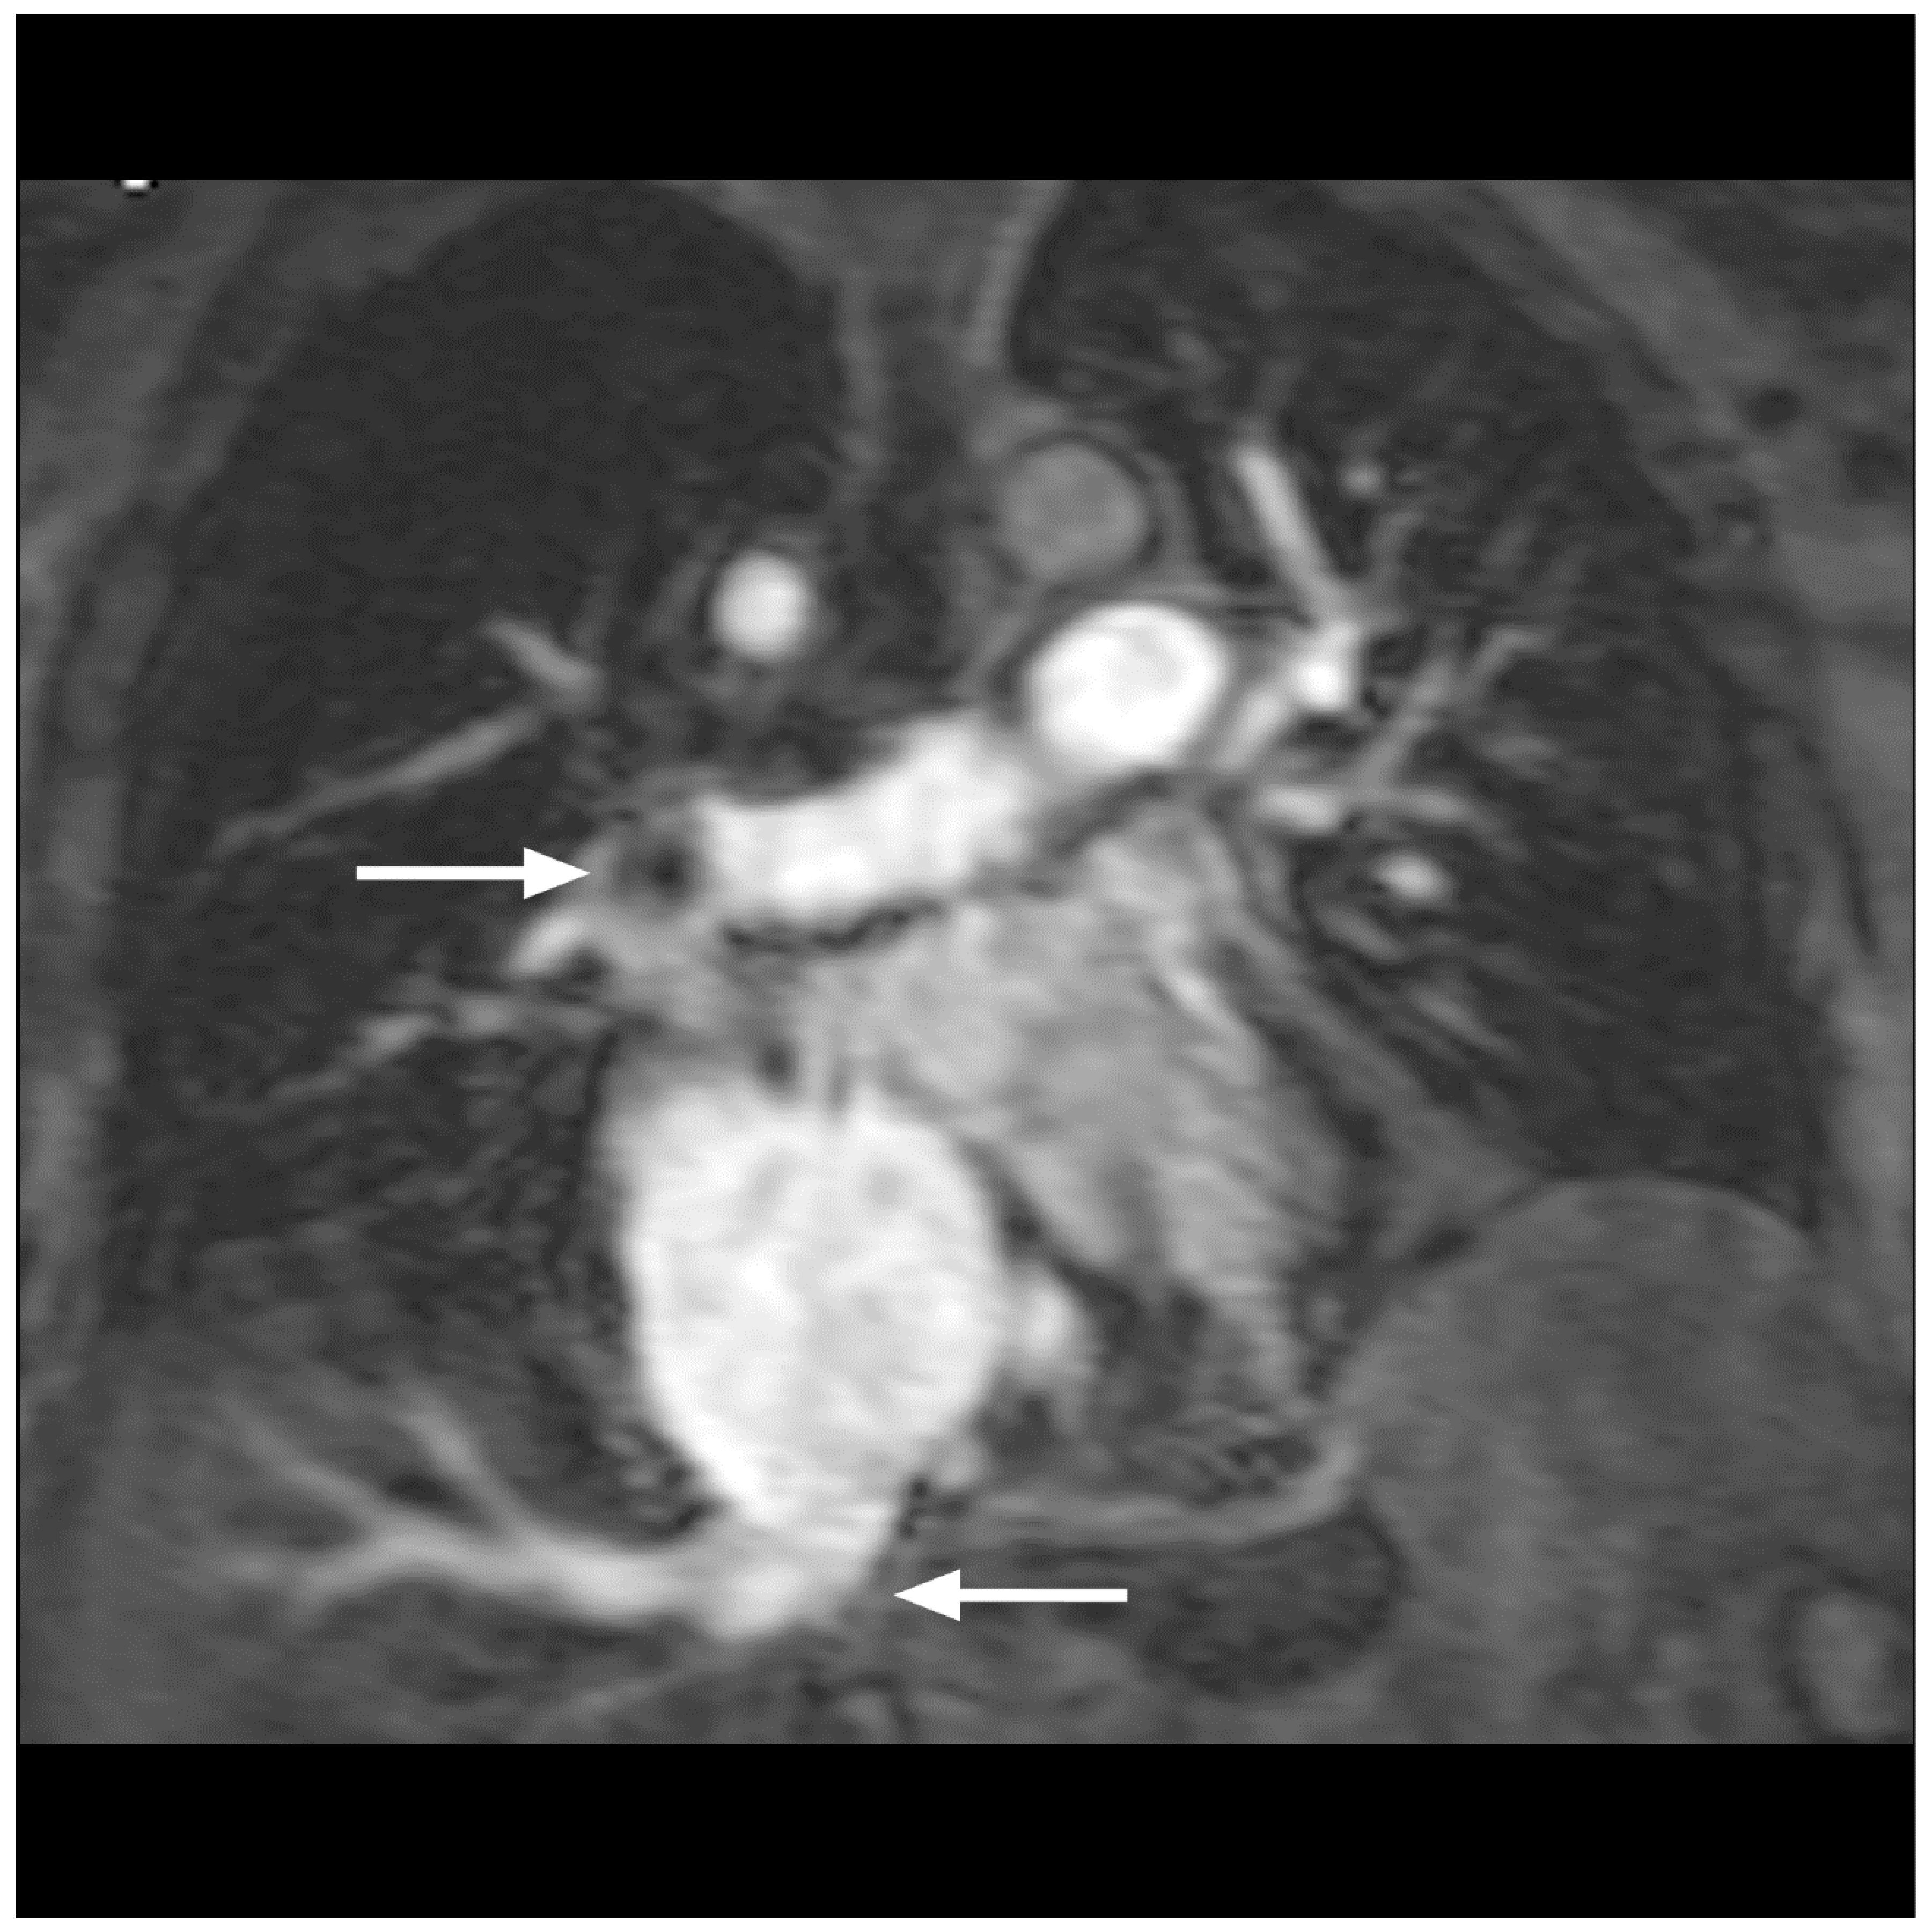

- Hansch, A.; Betge, S.; Poehlmann, G.; Neumann, S.; Baltzer, P.; Pfeil, A.; Waginger, M.; Boettcher, J.; Kaiser, W.A.; Wolf, G.; et al. Combined magnetic resonance imaging of deep venous thrombosis and pulmonary arteries after a single injection of a blood pool contrast agent. Eur. Radiol. 2011, 21, 318–325. [Google Scholar] [CrossRef]